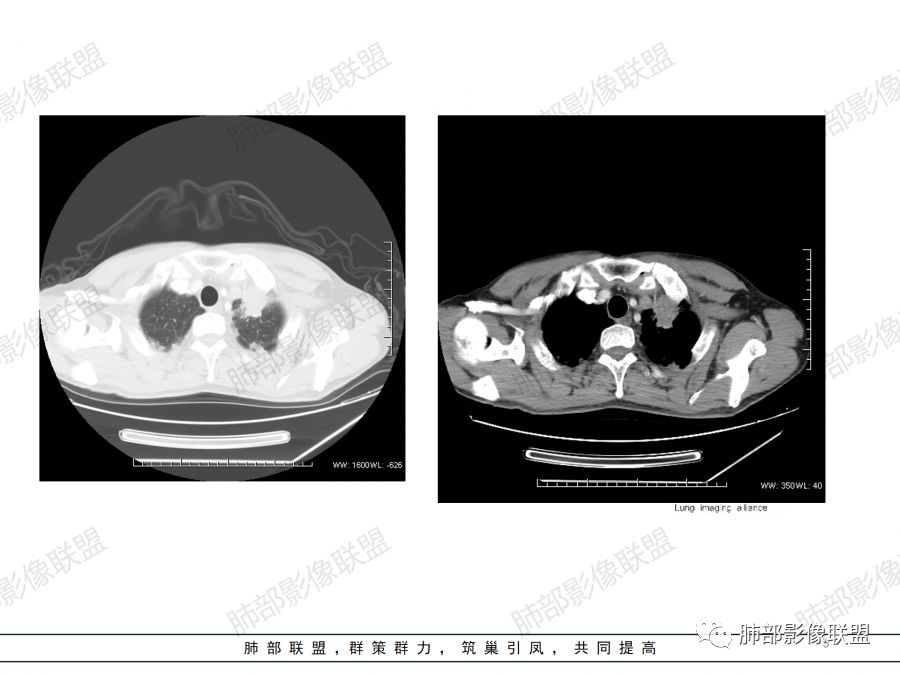

男性,47岁,咳嗽咳痰一月。

胸CT:左上叶前段团块影,边缘部分清晰,近纵隔侧膨隆明显,分叶,肺侧见平直征,U形凹陷,病灶周围可见磨玻璃影,气肿带,纵隔多发淋巴结肿大,叶间裂多发小结节。增强病灶内密度不均,散在斑片状低密度区,血管造影征。考虑:恶性,鳞?腺?大细胞?鉴别:炎症。似有左侧胸廓内A供血病灶,SFT?

1.左肺上叶尖后段体积变化不大,病灶长轴沿支气管血管束向肺门侧生长,

2.病灶外围大,内带小,外朝内蔓延

3.病灶边缘以收缩为主,局部稍膨隆,

4.病灶整体轻中度强化,强化较均匀,局部见多个管状低密度影,边界清,考虑支气管粘液栓;病灶局部可小灶样的低密度区,未见强化,考虑坏死灶,坏死灶周围见明显强化的壁,壁清楚、光整,未见中断,倾向炎性肉芽肿的坏死;

5.病灶内血管部分走形自然,部分走形僵直、粗细不均,提示病灶有部分破坏力,但是不强;

6.病灶与纵隔胸膜呈“糊墙”样改变,倾向炎性病灶;

6.纵隔淋巴结肿大,密度均匀,强化均匀;